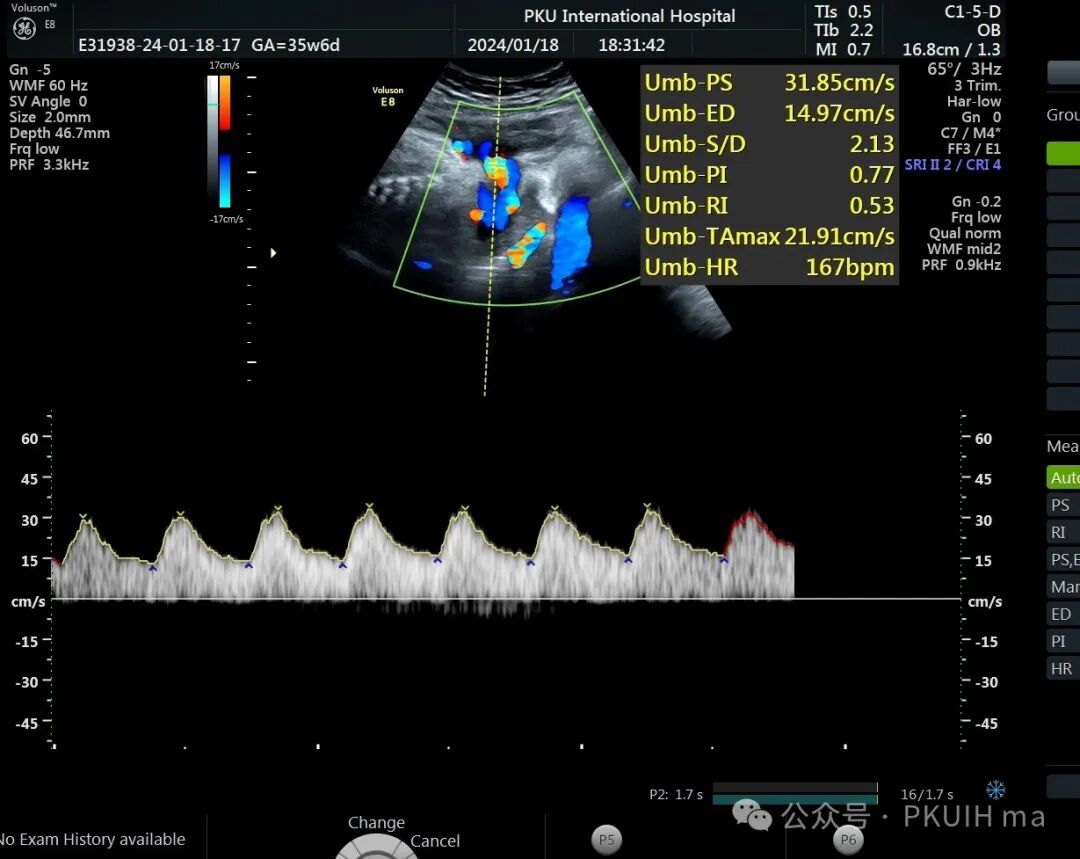

前两天碰到一孕妇胎动减少来诊,孕妇自述下午两点开始发现胎儿无明显胎动,吃了甜的食物和改变姿势还是不怎么动,随于下午六点左右来诊。超声发现胎儿绕颈两周以上且绕的较紧,检查中发现胎儿心率快,胎儿无明显胎动,绕颈处脐动脉血流加速时间延长,胎儿大脑中动脉阻力低,反复测量两侧大脑中动脉阻力均低。胎心监护也不好,随后产科采取紧急剖宫产。

脐带绕颈两周以上,绕的特别紧,感觉脖子都被勒细了,脐带与皮肤之间无任何空隙。绕颈处血流加速时间延长,说明可能存在交锁并出现了脐动脉局部狭窄